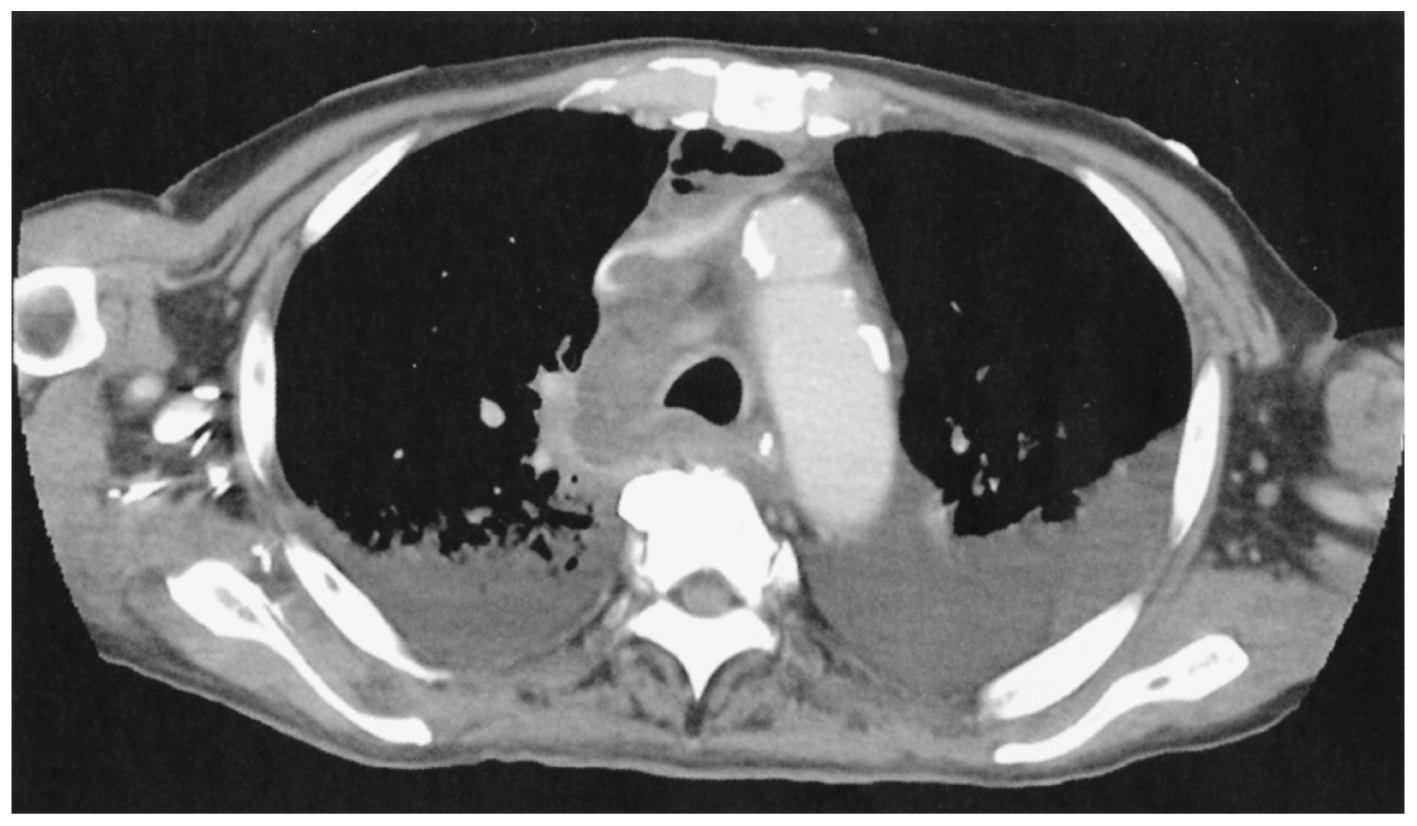

71歳の男性。呼吸困難を主訴に来院した。3日前から歯痛と咽頭痛があり,2日前から頸部の痛みと腫脹を伴い,昨夜から前胸部痛と呼吸困難を自覚したため受診した。既往歴に高血圧と2型糖尿病がある。体温38.9℃。脈拍100/分,整。血圧88/60mmHg。呼吸数28/分。SpO2 91%(room air)。頸部に圧痛と腫脹を認める。血液所見:白血球15,500。CRP 32mg/dL。胸部造影CTを下に示す。

無料会員登録していただくと、実際の解説をすべて見ることができます。急性の呼吸困難を主訴とする疾患としては,喉頭浮腫,気道異物,自然気胸,気管支喘息,慢性閉塞性肺疾患の急性増悪などの呼吸器疾患,心不全(急性,慢性の急性増悪),肺血栓塞栓症などの循環器疾患が代表的である。この症例では呼吸器感染症と心不全が疑われるが,胸部エックス線写真は肺炎像というよりも両心不全を示唆する所見を示している。診断:心不全(両心不全)(Nohria分類wet and warm) 選択肢考察 ×a 強い呼吸困難,胸痛などにより安静が保てない場合には,血管拡張による前負荷軽減と,交感神経抑制による心筋酸素消費量の減少を目的としてモルヒネを使用する。この症例ではモルヒネが必要となるほどの興奮状態ではない。